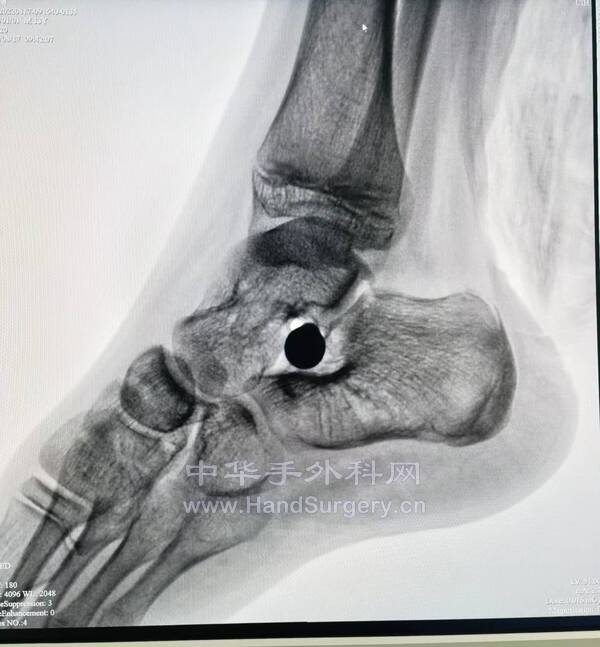

今日参与手术2台注意事项:

1.距骨囊肿:根据囊肿位置确定切口,显露距舟关节,观察关节面情况,如果可保留关节面,行切除植骨,如果不能保留,行距舟关节融合。